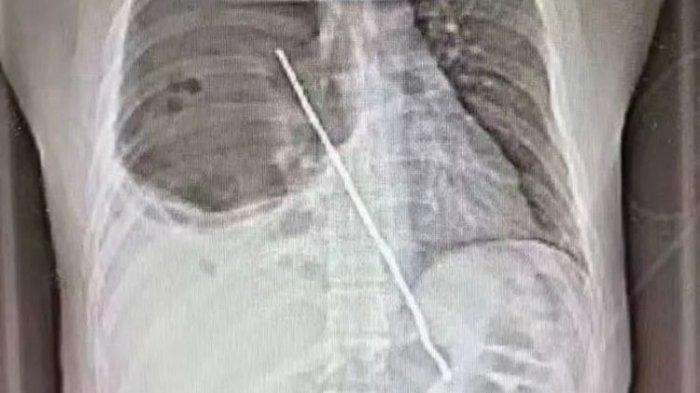

Seorang pria di barat laut China tak sengaja menelan tusuk sate dari besi, menembus tenggorokan dan paru-parunya.

Kepada petugas medis di gawat darurat Senin (10/5/2021), Zhang mengaku dia menelan batang sepanjang 8 inchi dalam keadaan mabuk.

Berdasarkan pemeriksaan pada torso, diketahui terdapat tusuk sate dari besi yang menancap di dada Zhang.

Dilansir Newsweek, batang itu sudah melubangi tenggorokan dan paru-paru, menyebabkan penumpukan cairan.

Dalam gambar yang dirilis, nampak batang tersebut menyentuh perut Zhang dan mendekati jantungnya.